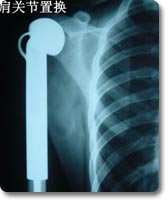

关节置换可以说是本世纪骨科手术最伟大的突破之一。目前它已应用於治疗肩关节、肘关节.腕关节、指间关节 、髋关节、膝关节及踝关节等疾患,但以全人工髋关节及膝关节置换最为普遍。对骨关节炎、股骨头无菌性坏死、老年性股骨颈骨折等疾病具有明显治疗效果,我科目前已开展各种置换手术800余例,疗效受到患者普遍肯定。 |